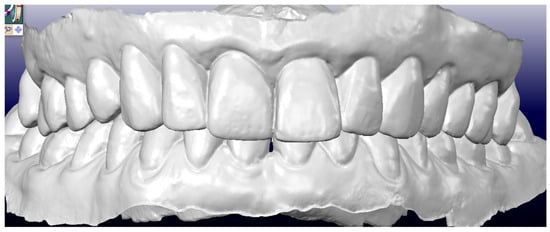

- Pretreatment occlusion scan using the iTeroTM 5.0 scanner, extracted into OrthoCAD 5.9.1.50 software (Align Technology, San Jose, CA, USA) (Figure 4), extra- and intraoral images taken with the Invisalign Practice App (Align Technology, San Jose, CA, USA) and pantomogram (Figure 5). Based on the iTeroTM 3D scan (Align Technology, San Jose, CA, USA) and occlusal examination, it was decided to use the Invisalign® system (Align Technology, San Jose, CA, USA) with the Express 1 arch subtype—the shortest possible treatment with seven aligners (and seven additional aligners) involving only the upper arch because the aim was to eliminate the occlusal injury of one tooth by its intrusion and a change of the anterior–posterior and mesiodistal inclination. The first treatment plan was performed using the ClinCheck 6.0 software (Align Technology, San Jose, CA, USA), which assumed movements of tooth 21—the main movement was a palatal inclination of the crown by 4.4 degrees, a distortion by 3.3 degrees and an intrusion by 0.4 mm (Figure 6). The analysis of this plan showed that it was impossible to eliminate the traumatic occlusion when changing the position of only one tooth in the arch (Figure 7)—the analysis showed numerous abnormal occlusal contacts.

Figure 4. Pretreatment occlusion scan performed using the iTeroTM 5.0 scanner, extracted into OrthoCAD 5.9.1.50 software: extraoral and intraoral images.